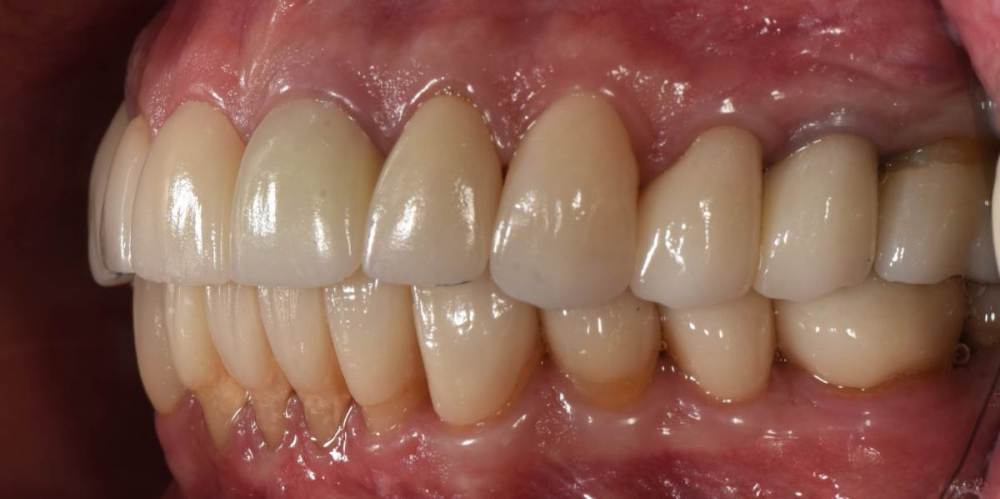

Финал работы:

DSC_3144.thumb.JPG.c9e60b8847f66dc01ba0e6e1113ab39b.JPGDSC_3145.thumb.JPG.1723748a079bc482f1a7e4534aff8f33.JPGDSC_3146.thumb.JPG.6dd4d0eb29dc3e6e92773c3c7892f692.JPGDSC_3147.thumb.JPG.e4f9cc2d841e3b7ff3aa73491ba9b4a3.JPGDSC_3148.thumb.JPG.0f174600adf2a49d65266a0ff665abfd.JPGDSC_3149.thumb.JPG.c9849be795d45b2573488d4545f3843f.JPGDSC_3150.thumb.JPG.6380366ecde7802fa32c6471b8b33883.JPGDSC_3153.thumb.JPG.1420d109d08ed1d6bd63447fe73eeed6.JPGDSC_3154.thumb.JPG.04b902149b3c0f9f2f1bcfa2e310c855.JPG

Фото спустя месяц после фиксации. Сначала нижняя челюсть, потом верхняя. Решение с передними нижними зубами - компромиссное. Все они витальные, имели 2-3 степень подвижности. После исправления положения нижней челюсти и установления правильных окклюзионных контактов - 1-2 степень подвижности. По поводу гигиены пытаемся.